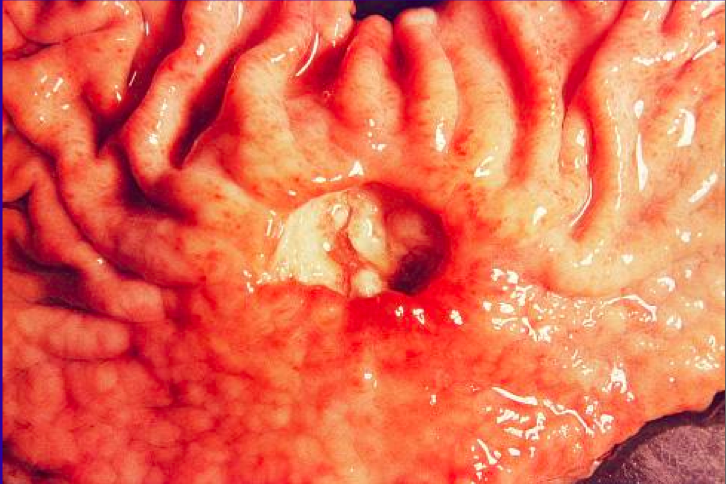

<p>Is this ulcer benign or malignant? Why do you say that?</p>

<p>malignant</p>

<ul>

<li>firm, elevated borders</li>

<li>irregular, necrotic base</li>

<li>no nice central congruence of rugae</li>

</ul>